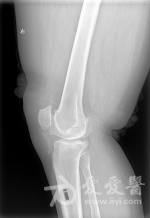

膝关节滑膜炎具体表现及中西医治疗方法大揭秘!慢性膝关节滑膜炎(chronic synovitis of knee joint)是骨科领域的基础疾病和常见疾病。 这种疾病是由于长时间的慢性劳损或滑膜炎在急性阶段没有得到及时和有效的治疗,促使滑膜细胞释放组织液体,进而逐渐使滑膜组织变得更为厚重和具有纤维化,实际上是一个由无菌性炎症反应触发的...

儿童膝关节滑膜炎病因及治疗方法大揭秘!滑膜组织充血、水肿,分泌大量炎性因子,导致滑膜组织增生,血管易化,表现为患膝关节肿胀,疼痛,功能障碍。 临床工作中,儿童膝关节滑膜炎不少见,但由于缺乏典型的临床表现,实验室检查及影像学检查特异性欠佳,致使疾病的性质难以确定,常造成误诊而延迟治疗时机。 目前该疾病多以保...